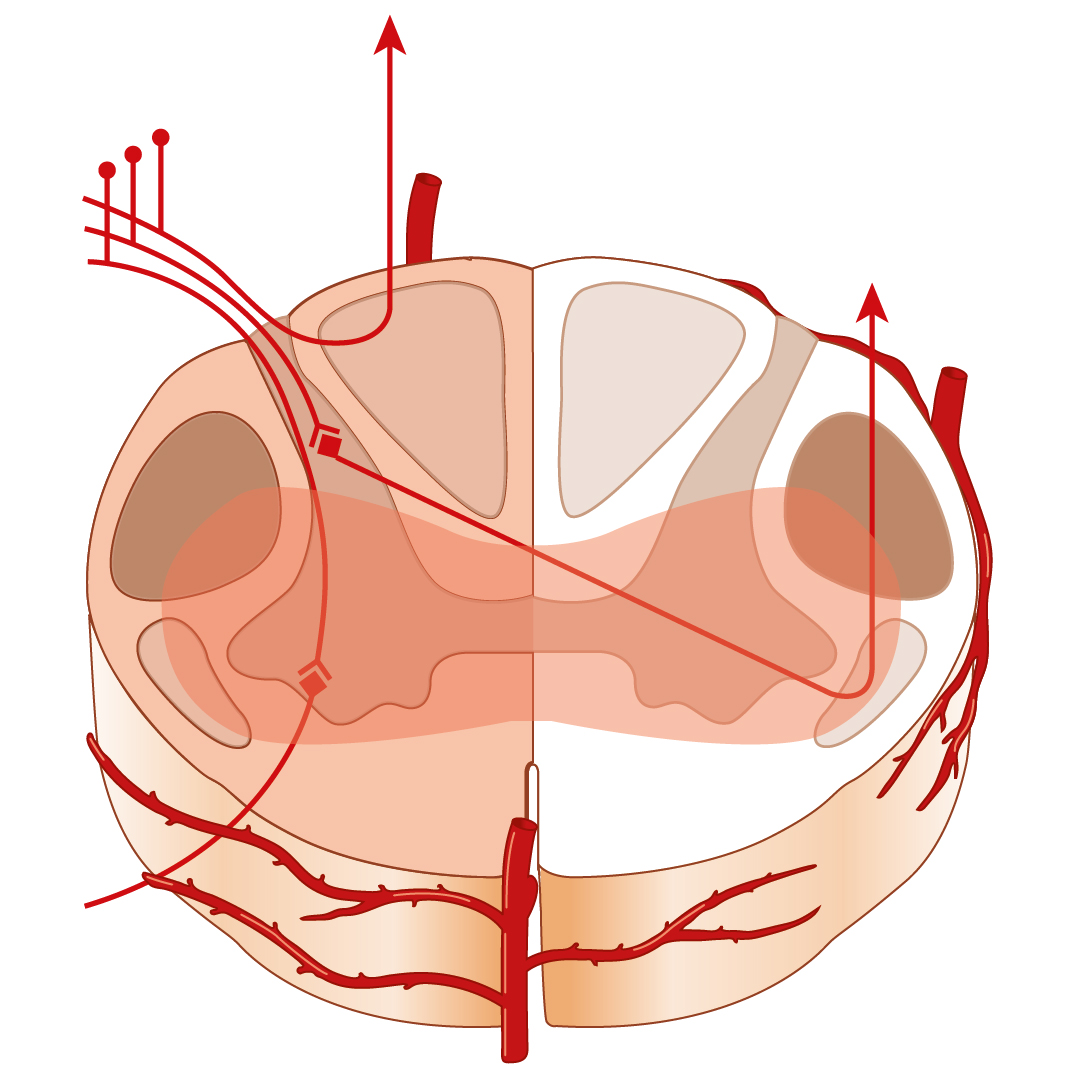

Medizinische Zeichnungen und Kinderbuch Illustration

Herzlich willkommen! Ich bin Ihre Expertin für medizinische Illustrationen und kreative Kinderbuch-Illustrationen. Mit einem Auge für wissenschaftliche Genauigkeit und einer Liebe zur Gestaltung kindgerechter Erzählwelten schaffe ich Bilder, die informieren und begeistern. Entdecken Sie mein Portfolio und lassen Sie sich von meiner Arbeit überzeugen!